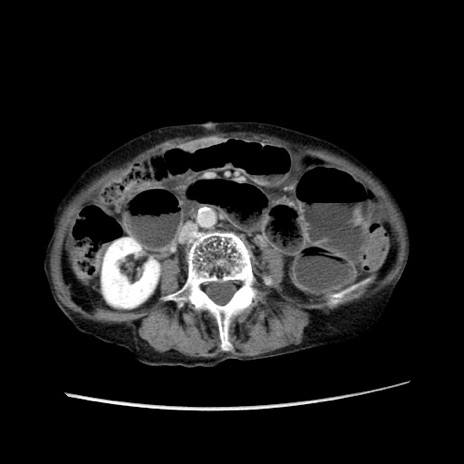

症例25(横断像)

【症例】80歳代女性

【主訴】胸のつかえ感

【現病歴】約9時間前に食後から胸のつかえた感じあり、嘔吐あり、来院。

【既往歴】胃癌(全摘)、胆摘、虫垂炎

【身体所見】心窩部に圧痛あり、反跳痛なし。

【データ】WBC 5700、CRP 0.05